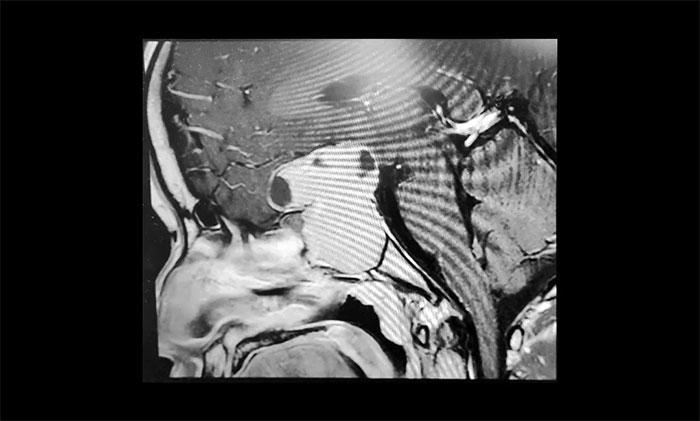

▲ 術(shù)前影像:巨大垂體瘤,向鞍上生長

為了進一步確定瘤體的位置和大小,當即進行了鞍區(qū)MRI平掃+增強。影像顯示,蝶鞍顯著擴大,鞍區(qū)見一“塔樣”腫塊灶,病變總矢橫高徑約3.5×4.5×5cm。瘤體向鞍上生長,占據(jù)鞍上池,明顯推移視交叉、分界模糊,三腦室前下部受壓變形。鞍底塌陷、蝶竇填充;侵及包繞兩側(cè)海綿竇約1/2,海綿竇向外側(cè)移位。

結(jié)合影像檢查,潘仁龍主任、李士其教授會診后一致達成共識。由于巨大垂體瘤長期壓迫視神經(jīng),患者視物出現(xiàn)異常,右眼已經(jīng)失明,手術(shù)指征明顯,應盡快手術(shù),盡可能挽救患者視力。